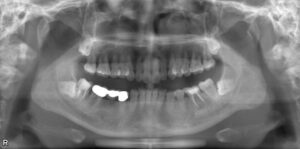

下顎小臼歯1本欠損症例

BEFORE AFTER 44歳女性/下顎1本欠損/インプラント埋込手術 【治療内容】 右下第二小臼歯は元々ブリッチが入…